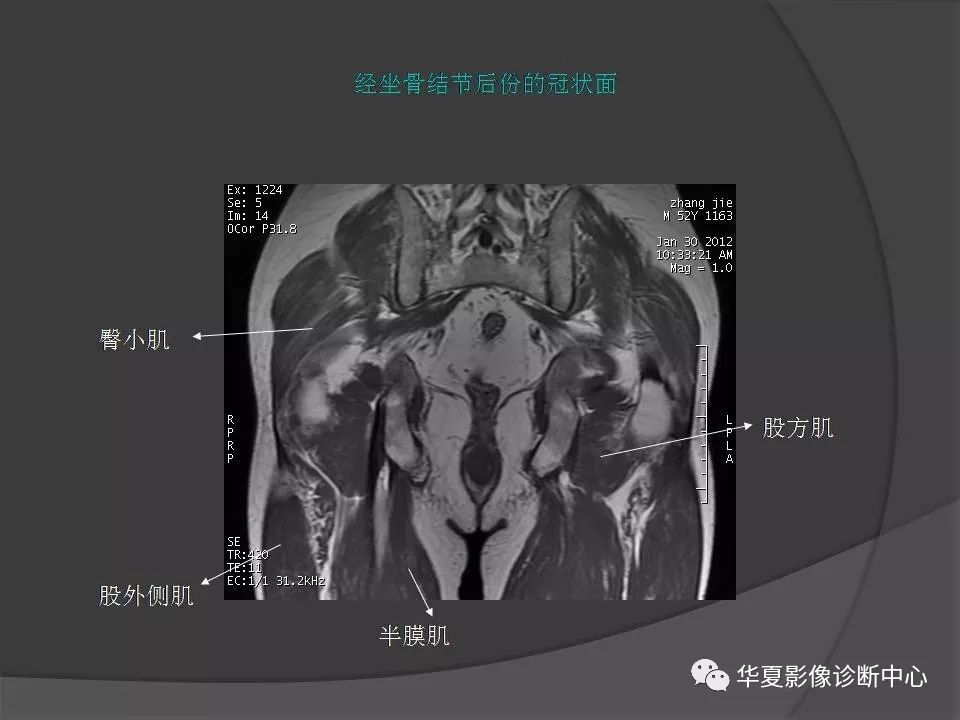

女性盆腔ct连续断层解剖图,盆腔mri影像病例分析